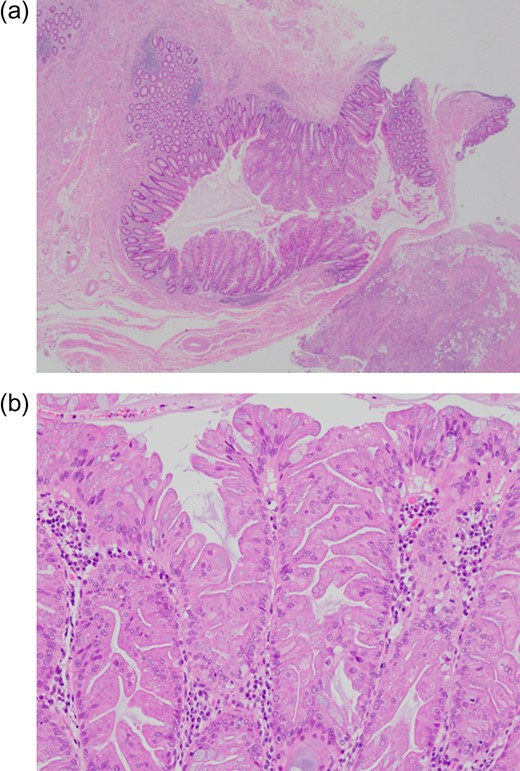

Pathological examination revealed that acute appendicitis and inflammatory adhesions with the ileum led to SBO. There were no other potential triggers of appendiceal foramen obstruction (such as a fecalith) other than a pedunculated polyp, that is ~5 mm in size (Fig. 2a and b). A histopathological examination of the polyp demonstrated that the long fronds of the adenoma were lined by dysplastic epithelial cells characterized by nuclear pleomorphism interspersed with cells containing dystrophic goblet cell vacuoles (Fig. 3a and b); however, there was no evidence of malignancy or invasive growth, in addition to the absence of matured irregular crypts toward normal-appearing nuclei. A pathological examination of the appendix revealed acute inflammation with neutrophil infiltration; the adhesions to the ileum were mainly inflammatory in nature, and no malignancy was observed. On the basis of the clinical course, he was diagnosed with a case of acute appendicitis triggered by the TSA of the appendiceal foramen leading to SBO.

(a and b) Formalin-fixed resected tissue shows no other potential cause of appendiceal foramen obstruction (such as a fecalith) other than a pedunculated polyp that is ~5 mm in size.

(a and b) Histopathological examination of sections of the polyp showing long fronds of the adenoma lined by dysplastic epithelial cells characterized by nuclear pleomorphism and elongated finger-like villous projections.